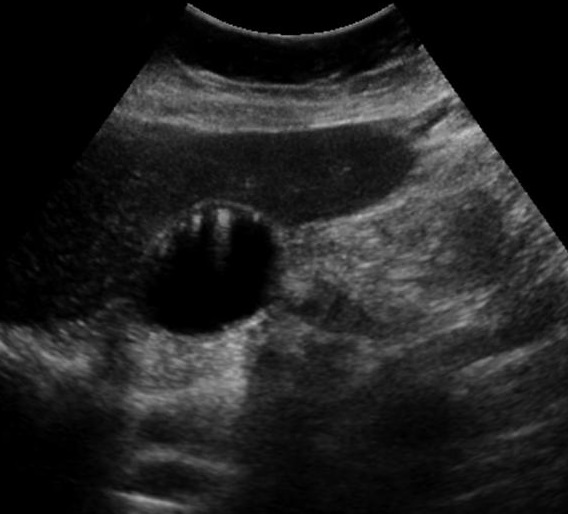

Adenome pedicule

de forme tubulaire . Aspect de adenomeme est

isoechogenique colletant au paroi par une pedicule .

Image echographique en coupe longitudinale de la

vesicule biliaire |